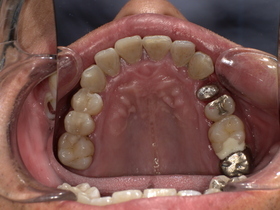

症例結果|Before / After

After

- 自然な白さ

- 違和感ゼロ

- 美しく機能的

👉 見た目も機能も大きく改善

治療詳細

- 年齢:50代男性

- 期間:約2週間(2回)

- 費用:セラミックジルコニア冠198,000円(税込)

土台 44,000円(税込)